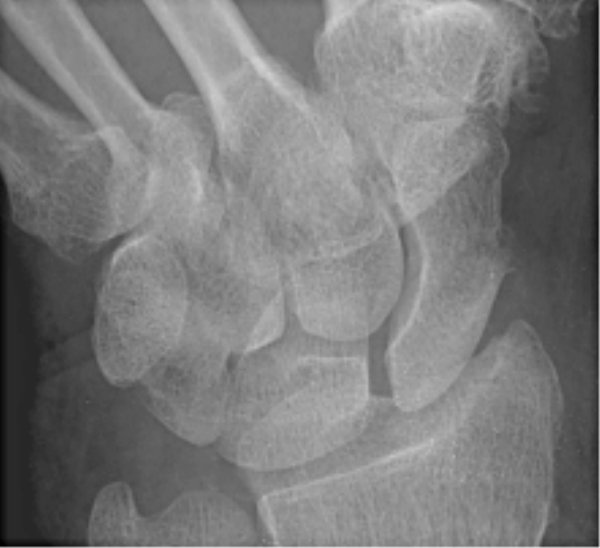

Return to Scaphoid Fracture